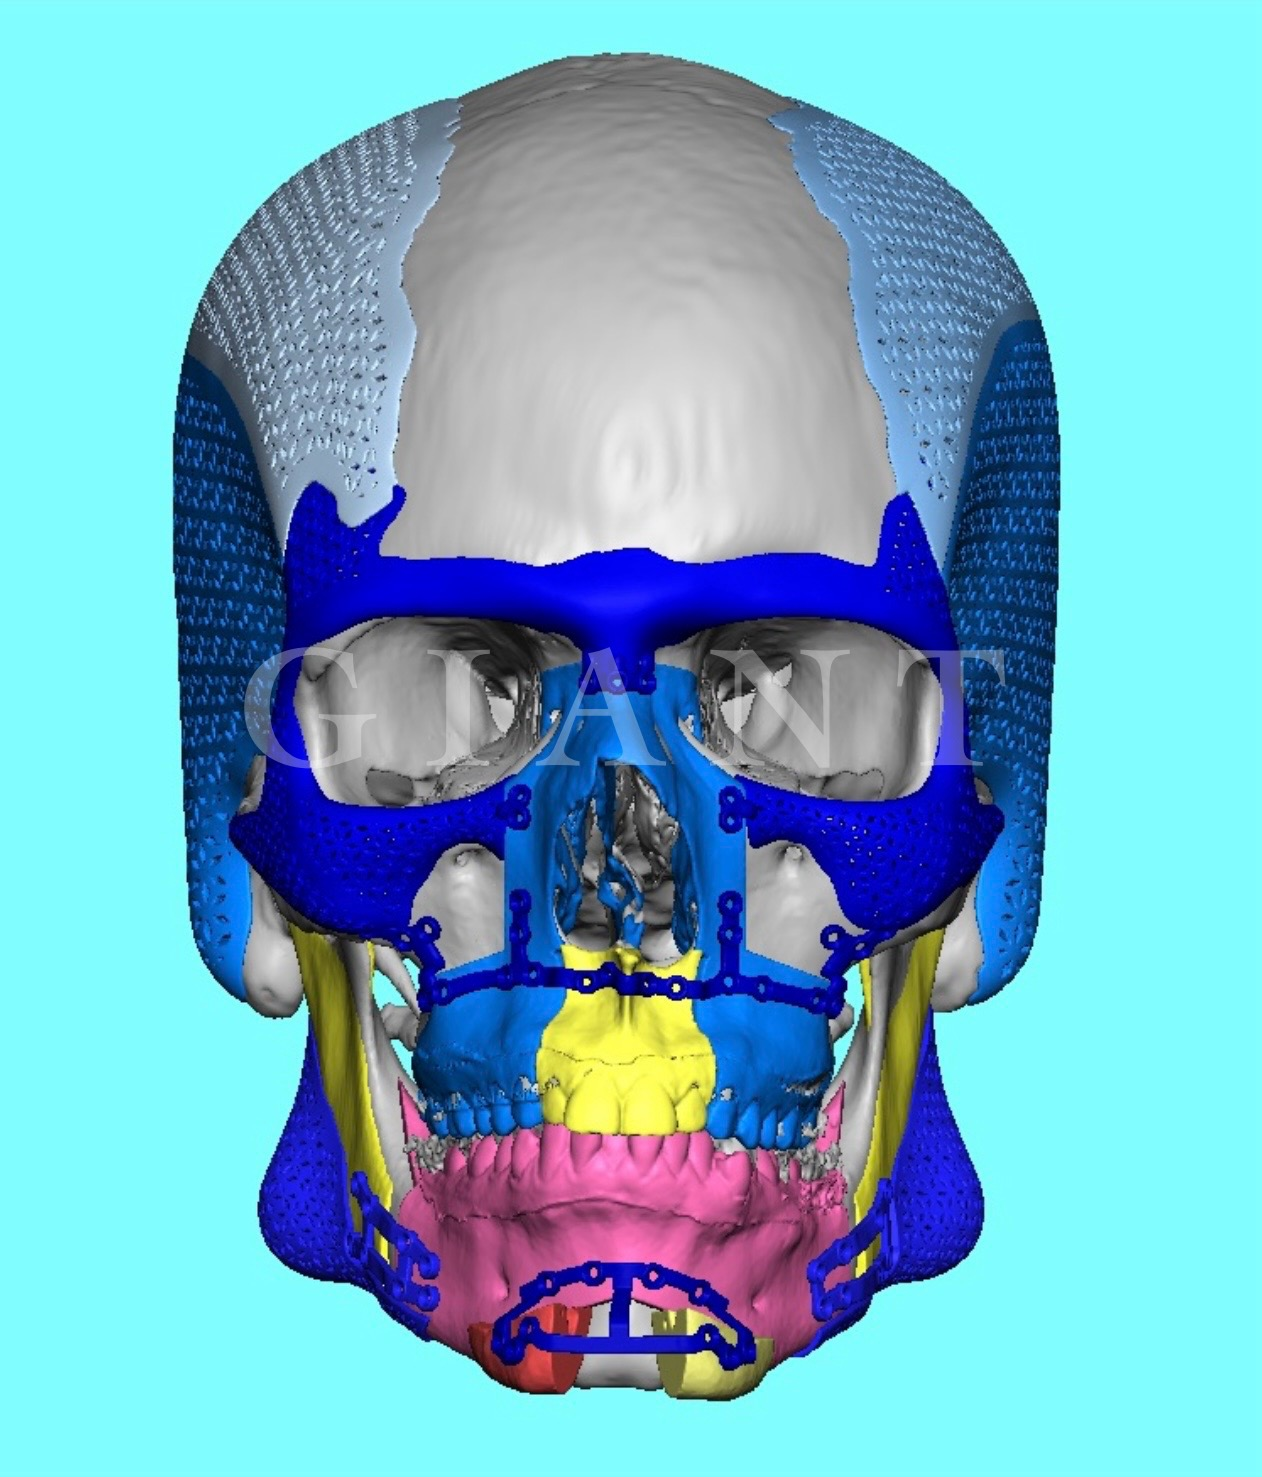

I just dont see any reason to bonesmash when we can do thisIts backed up by Science and I've seen hundreds of transformations on Discord

I have $7.56 in my Bank account bro.I just dont see any reason to bonesmash when we can do this

View attachment 4210290View attachment 4210293